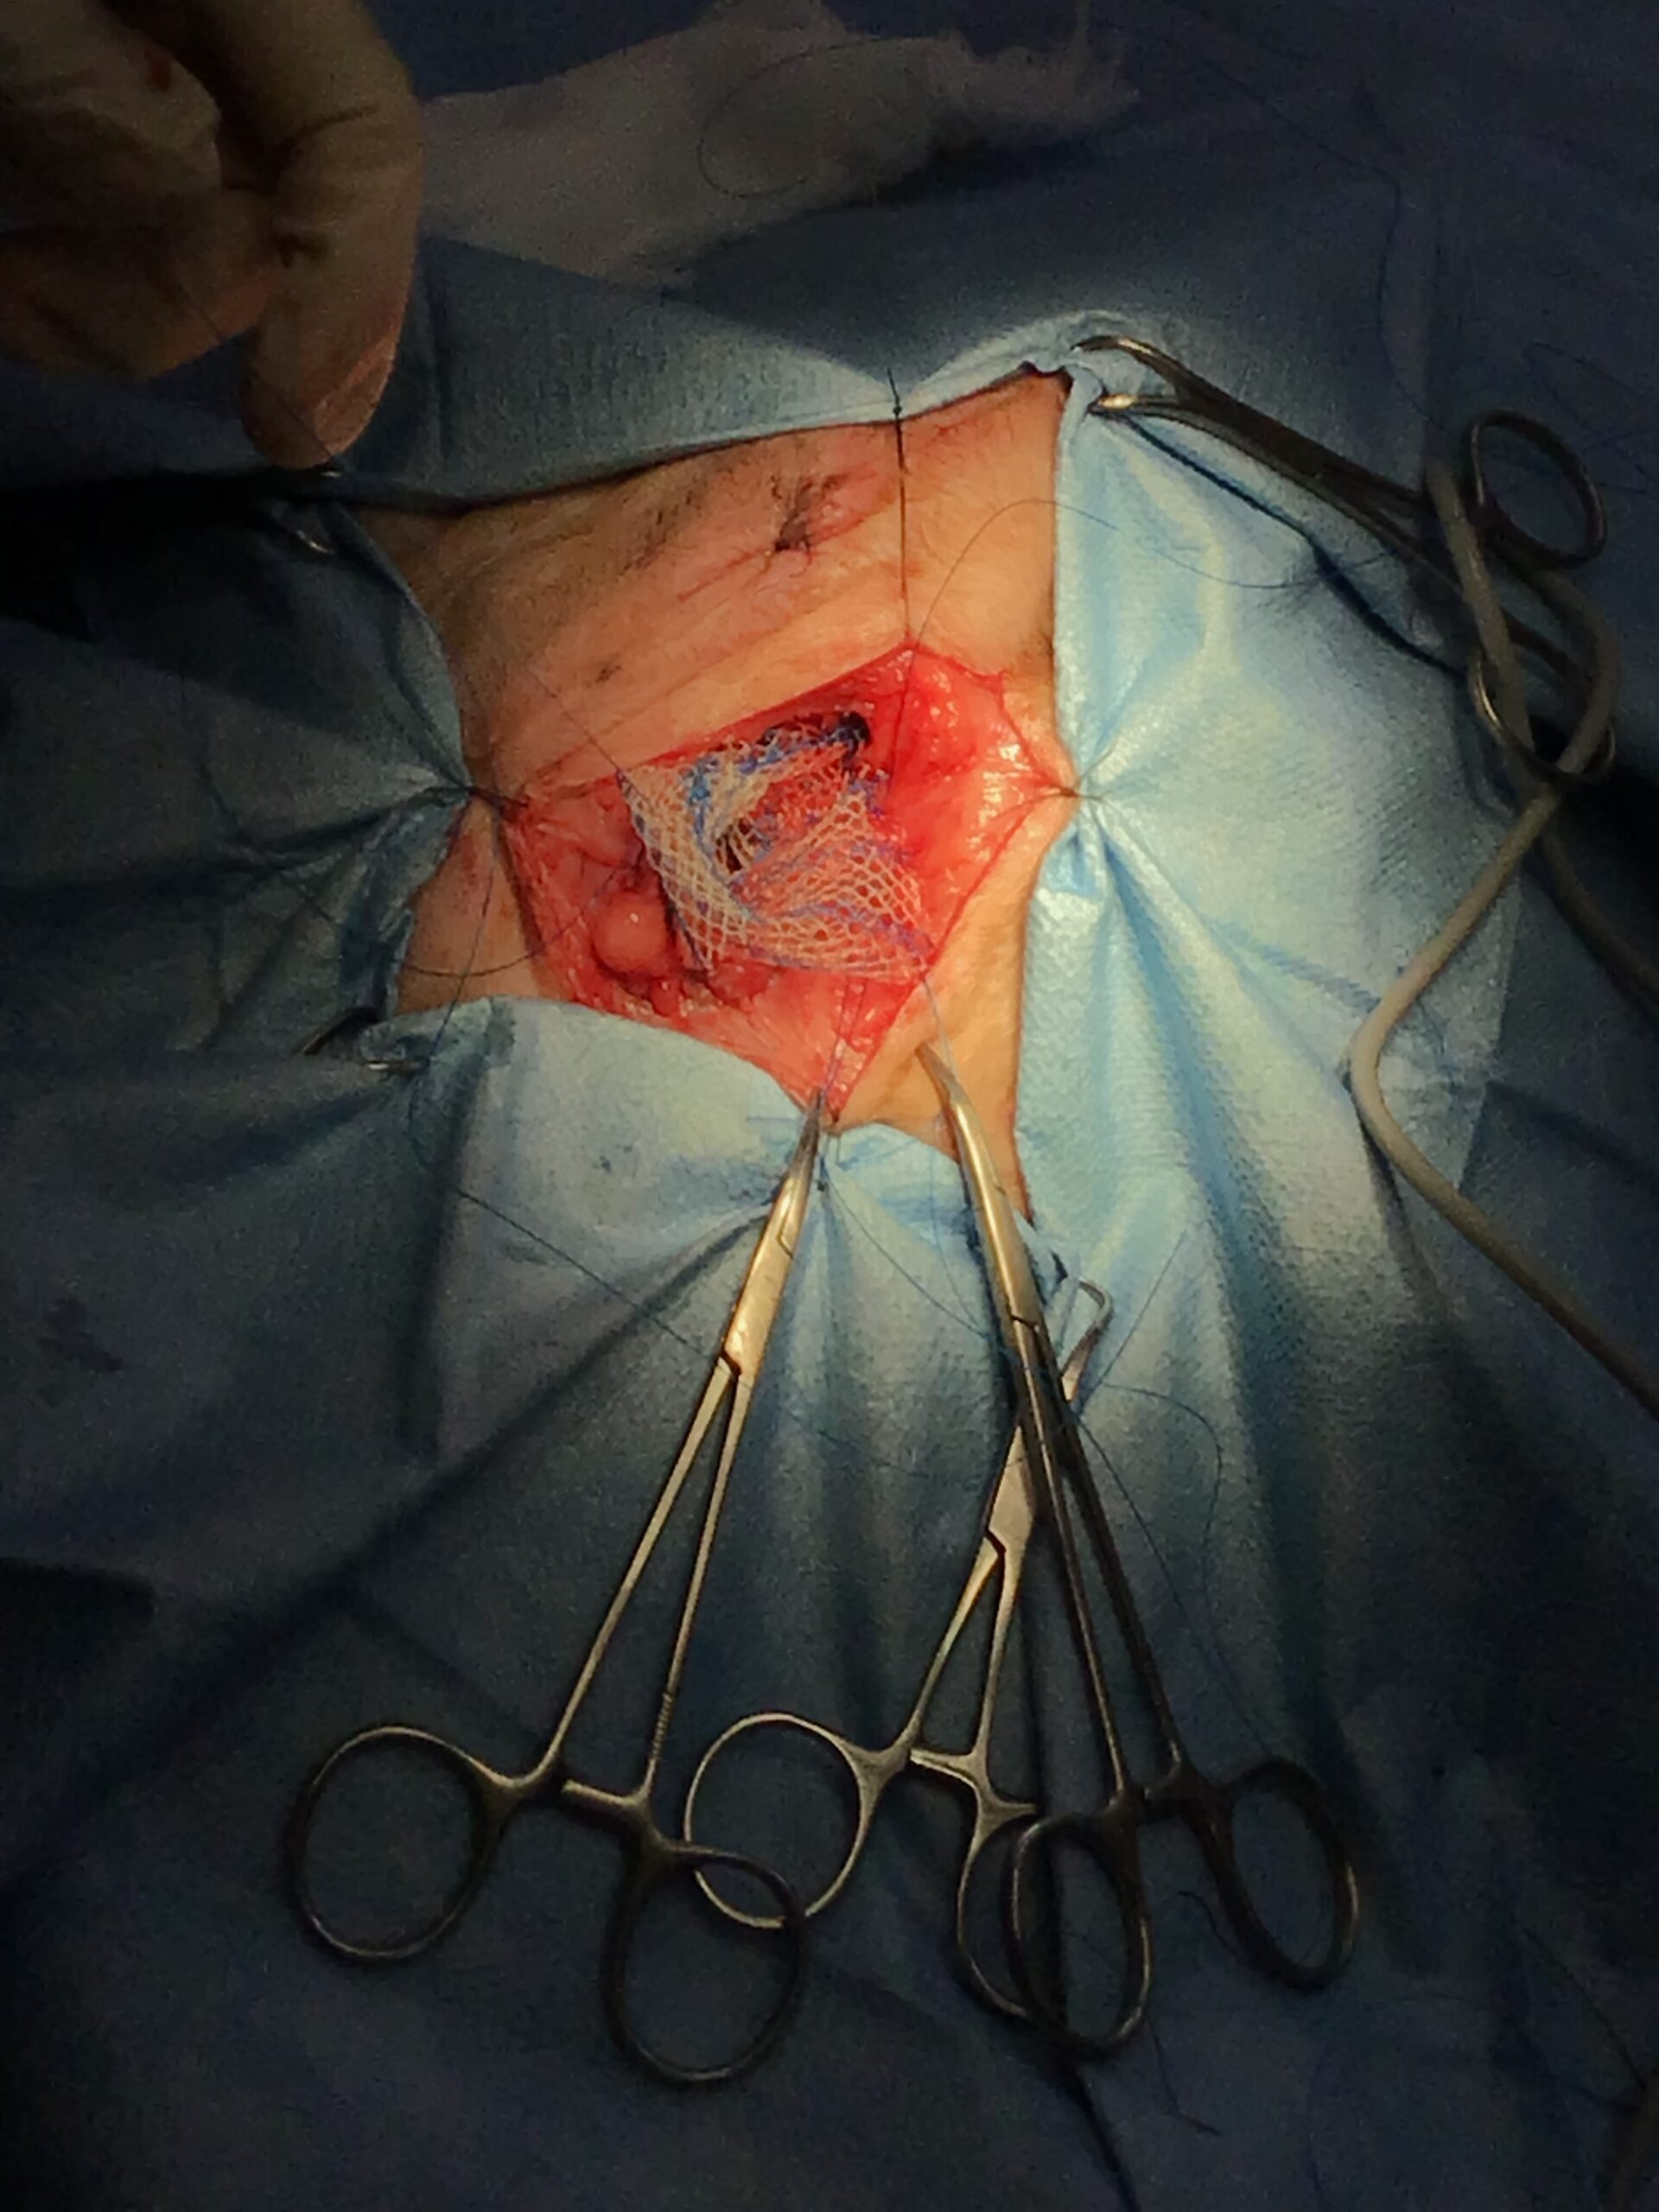

本症例には、時期を分けて2つの大きな外科的介入を行いました。

【致死的合併症】メッシュ縫合時に坐骨神経を巻き込んだ場合、術直後から後肢の永久的な神経麻痺(ナックリング)が生じ、直ちに再手術が必要です。また、メッシュへの重度感染や、直腸・前立腺の損傷による化膿性腹膜炎は致死的となります。

This post details our surgical and medical approach to a complex case involving recurrent severe perineal hernia and a malignant liver lymphoma in a senior dog. We emphasize the grim reality of untreated conditions and the severe risks of anesthesia when underlying heart and respiratory diseases are present. To maximize safety, we exclusively use local infiltration anesthesia. Due to a lack of available autologous tissue, a polypropylene mesh and extensive organ pexy (both colon and bladder fixation to the abdominal wall) were required to prevent fatal urethral obstruction and re-herniation. Additionally, simultaneous castration was performed to shrink the enlarged prostate, a key factor in hernia development, thereby reducing the risk of recurrence. For the liver tumor, given its deep location at the liver base and the high risk of fatal bleeding, we opted for a biopsy which confirmed lymphoma. Unfortunately, the patient’s elevated bilirubin and the family’s preference for a compromised, single-agent chemotherapy protocol led to early drug resistance. We candidly discuss the harsh realities of end-stage cancer—it is a painful decline characterized by severe cachexia and organ failure that palliative care can only partially ease. Furthermore, we outline our strict early discharge policy (1-3 days), the physical limitations of our unstaffed overnight remote monitoring, and our referral policy for highly specialized surgeries. We believe in providing honest, logical medical facts rather than false hope, ensuring families can make fully informed and responsible decisions.